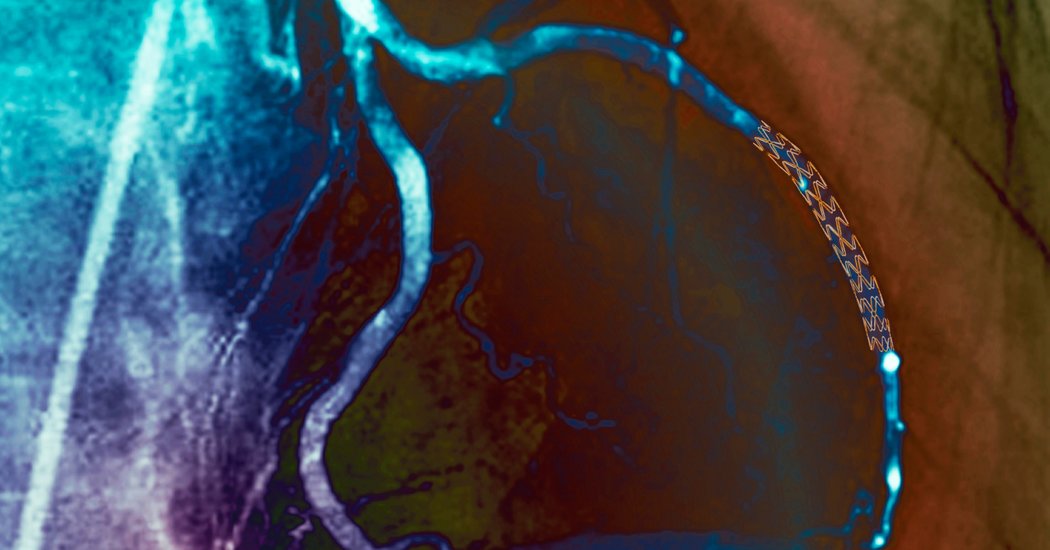

Credit…Zephyr/Science Source

The new study found that patients who received drug therapy alone did not experience more heart attacks or die more often than those who also received bypass surgery or stents, tiny wire cages used to open narrowed arteries.

That finding held true for patients with several severely blocked coronary arteries. Stenting and bypass procedures, however, did help some patients with intractable chest pain, called angina.